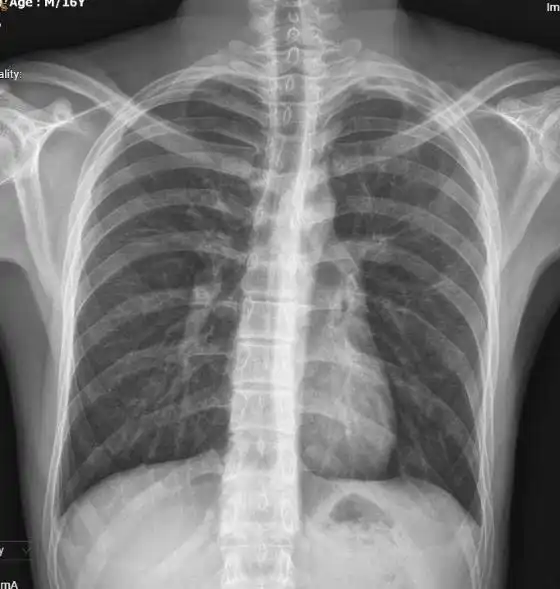

Đến ngày điều trị thứ 11, không còn ghi nhận khí thoát ra qua ống dẫn lưu. Hình ảnh X-quang và cắt lớp vi tính (CLVT) ngực xác nhận phổi nở hoàn toàn, không còn hình ảnh tràn khí màng phổi và không phát hiện kén khí tồn lưu. Căn cứ vào diễn biến lâm sàng và cận lâm sàng ổn định, ống dẫn lưu được rút an toàn. Người bệnh được xuất viện sau 12 ngày điều trị trong tình trạng ổn định.

Cắt lớp vi tính (CLVT) ngực trước thời điểm rút dẫn lưu và X-quang ngực sau rút dẫn lưu cho thấy phổi nở tốt, không còn hình ảnh tràn khí trong khoang màng phổi. |